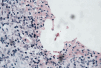

Fig. 2. Histología del nódulo. Se observan histiocitos epitelioides y abundantes neutrófilos alrededor de un espacio claro con abundantes bacilos extracelulares.